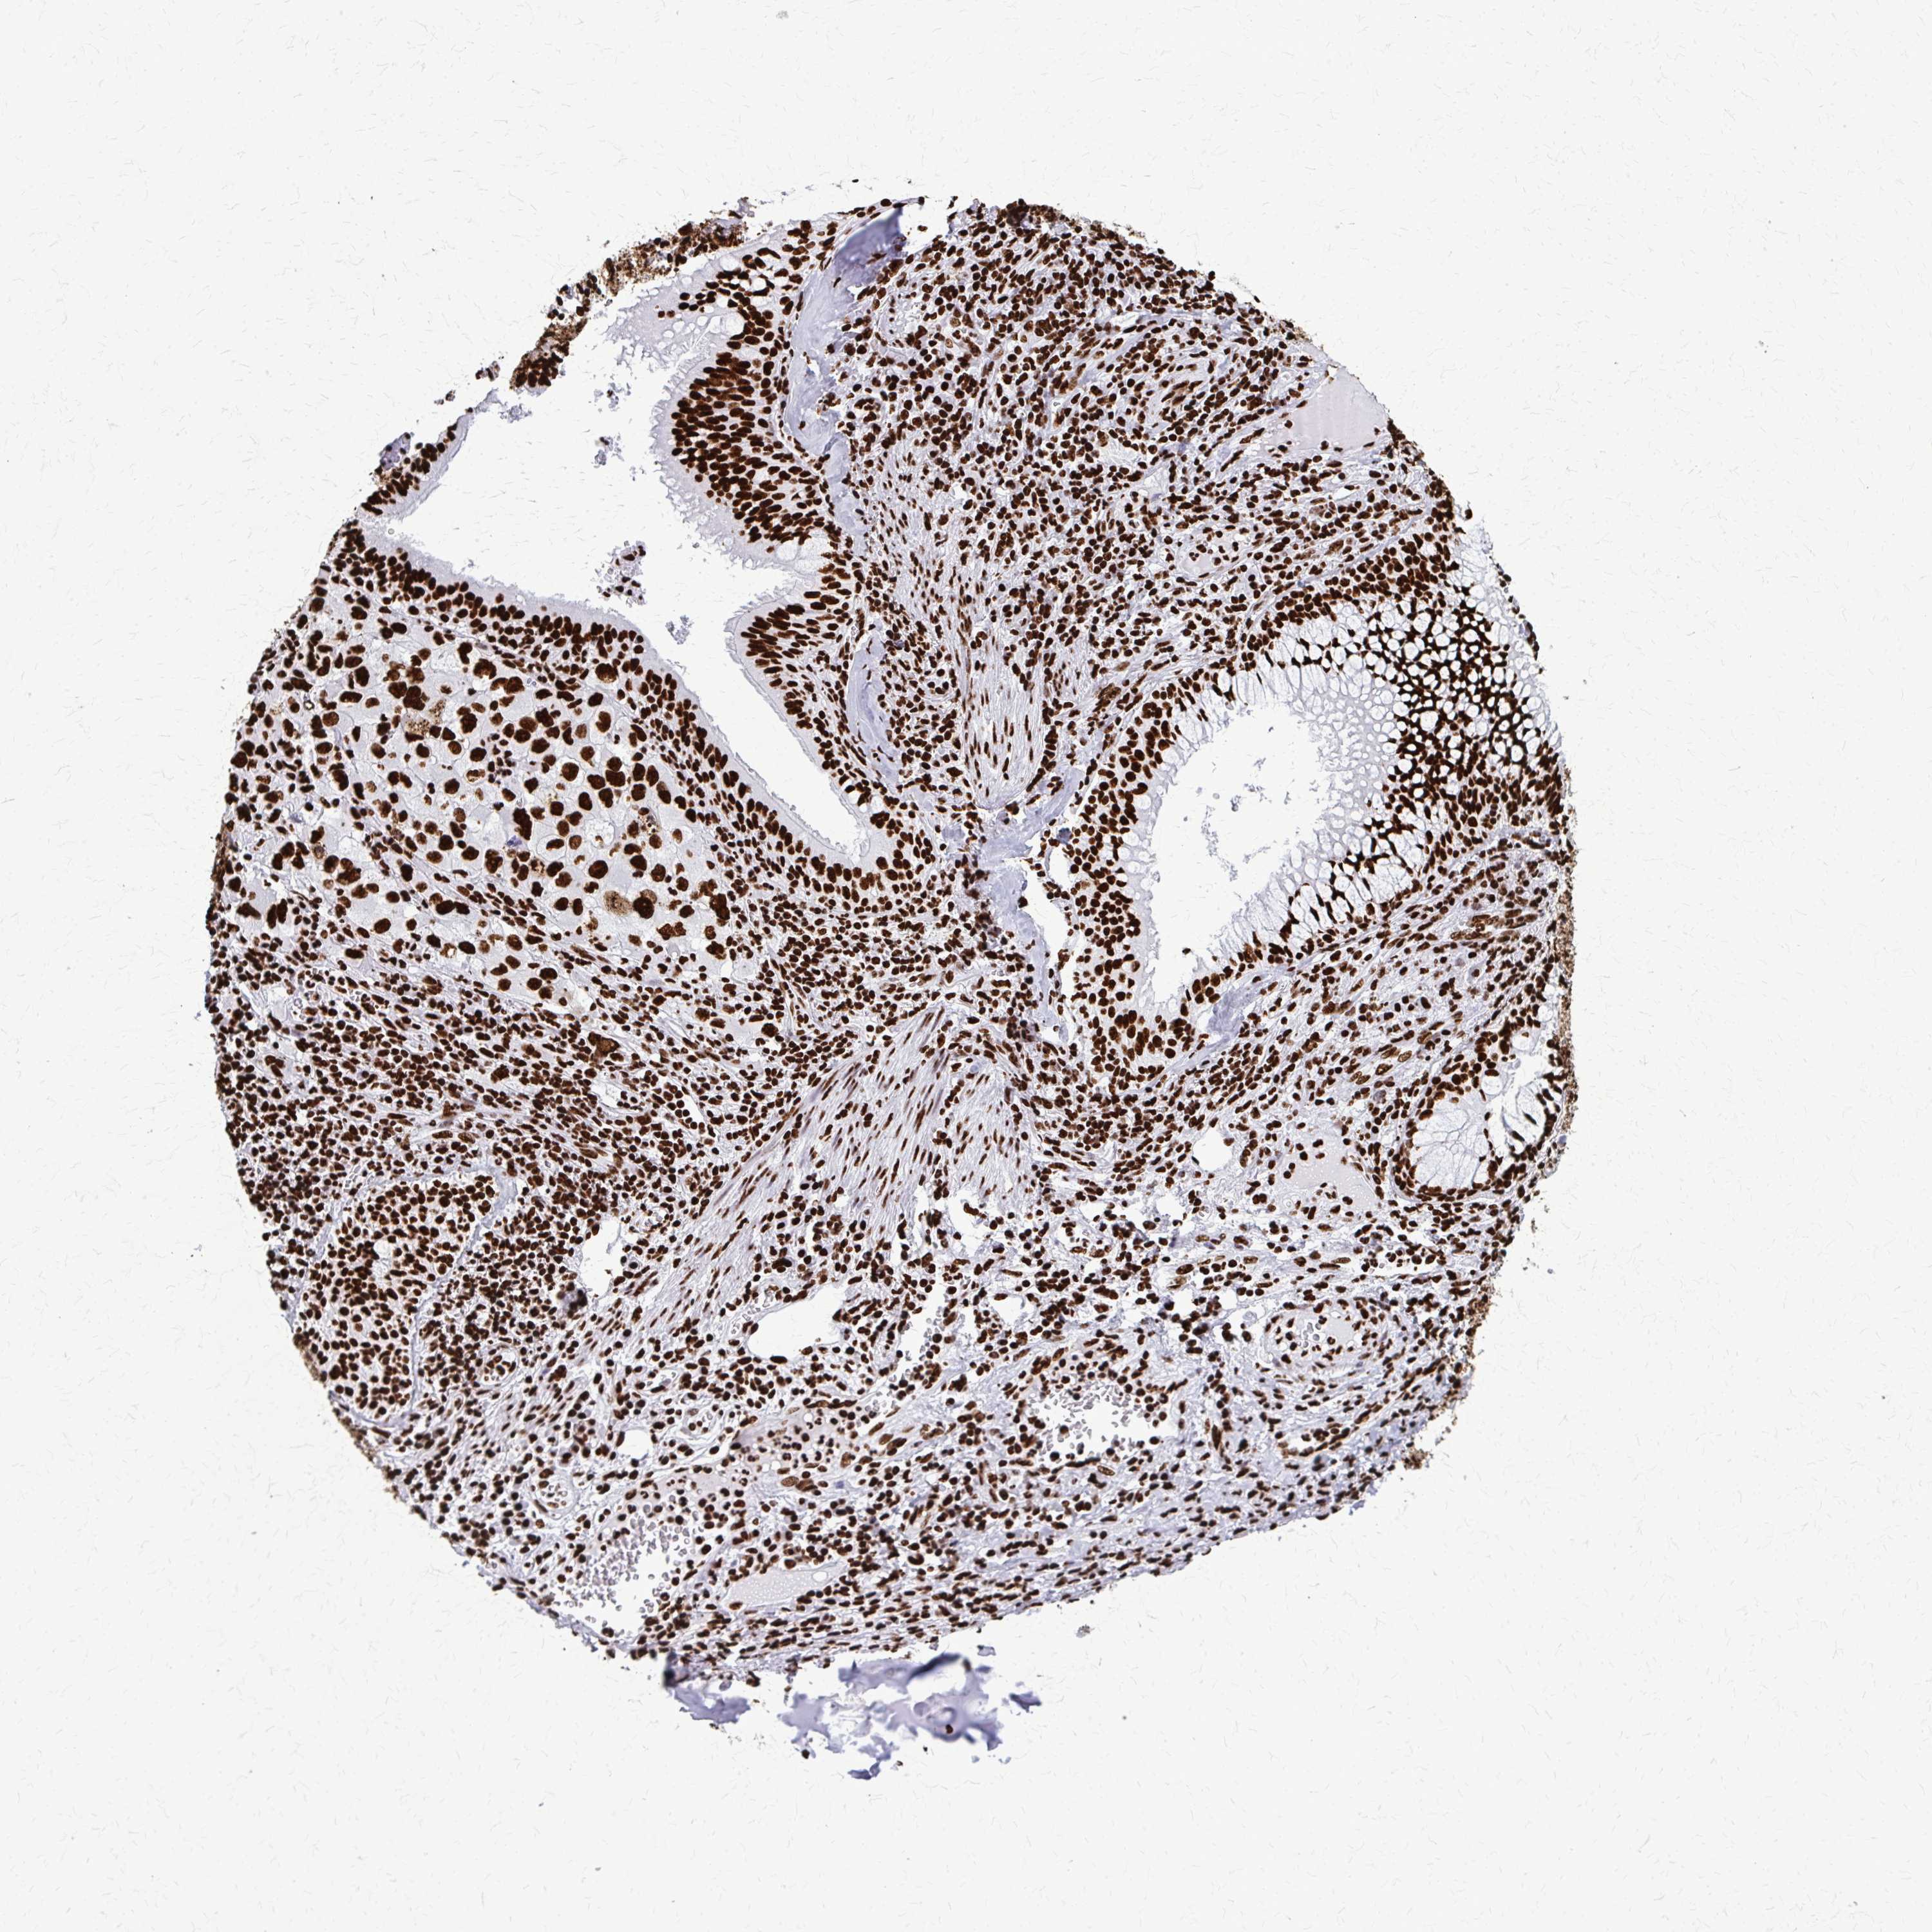

LUNG SQUAMOUS CELL CARCINOMA (TCGA) - Interactive survival scatter ploti

The Survival Scatter plot shows the clinical status (i.e. dead or alive) for all individuals in the patient cohort, based on the same data that underlies the corresponding Kaplan-Meier plots. Patients that are alive at last time for follow-up are shown in blue and patients who have died during the study are shown in red.

The x-axis shows the expression levels (FPKM) of the investigated gene in the tumor tissue at the time of diagnosis. The y-axis shows the follow-up time after diagnosis (years). Both axes are complimented with kernel density curves demonstrating the data density over the axes. The top density plot shows the expression levels (FPKM) distribution among dead (red) and alive patients (blue). The right density plot shows the data density of the survived years of dead patients with high and low expression levels respectively, stratified using the cutoff indicated by the vertical dashed line through the Survival Scatter plot. This cutoff is automatically defined based on the FPKM cutoff that minimizes the p-score. The cutoff can be changed by dragging the vertical line or by entering a cutoff value in the square labeled "Current cut-off".

Under the Survival Scatter plot the p-score landscape (black curve; left axis) is shown together with dead median separation (red curve; right axis). Dead median separation is the difference in median mRNA expression between patients who have died with high and low expression, respectively. It is calculated as follows: median FPKM expression of dead patients with high expression - median FPKM expression of dead patients with low expression. This is intended to aid the user in visually exploring custom cutoffs and the associated p-scores and dead median separation.

Individual patient data is displayed and can be filtered by clicking on one or more of the category buttons on the top of the page. Categories describing expression level and patient information include: high, low, alive, dead, female, male and tumor stages. The scale of the x-axis can be toggled between linear and log-scale by clicking on the "x log" button. Mouse-over function shows TCGA ID, patient information and mRNA expression (FPKM) for each patient.

& Survival analysisi

Kaplan-Meier plots summarize results from analysis of correlation between mRNA expression level and patient survival. Patients were divided based on level of expression into one of the two groups "low" (under cut off) or "high" (over cut off). X-axis shows time for survival (years) and y-axis shows the probability of survival, where 1.0 corresponds to 100 percent.

SFPQ is not prognostic in Lung Squamous Cell Carcinoma (TCGA)

: 64.38

P scorei

N/A

Average pTPM 80.8

Number of samples 489